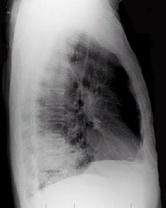

男性,62岁,咳嗽、胸痛一月,X线检查如图,最佳的诊断是 ( )A、右肺转移瘤B、右胸腔积液C、右下肺不张D、右肺癌E、右下肺炎症

问题 男性,62岁,咳嗽、胸痛一月,X线检查如图,最佳的诊断是 ( )

选项 A、右肺转移瘤 B、右胸腔积液 C、右下肺不张 D、右肺癌 E、右下肺炎症

答案 D